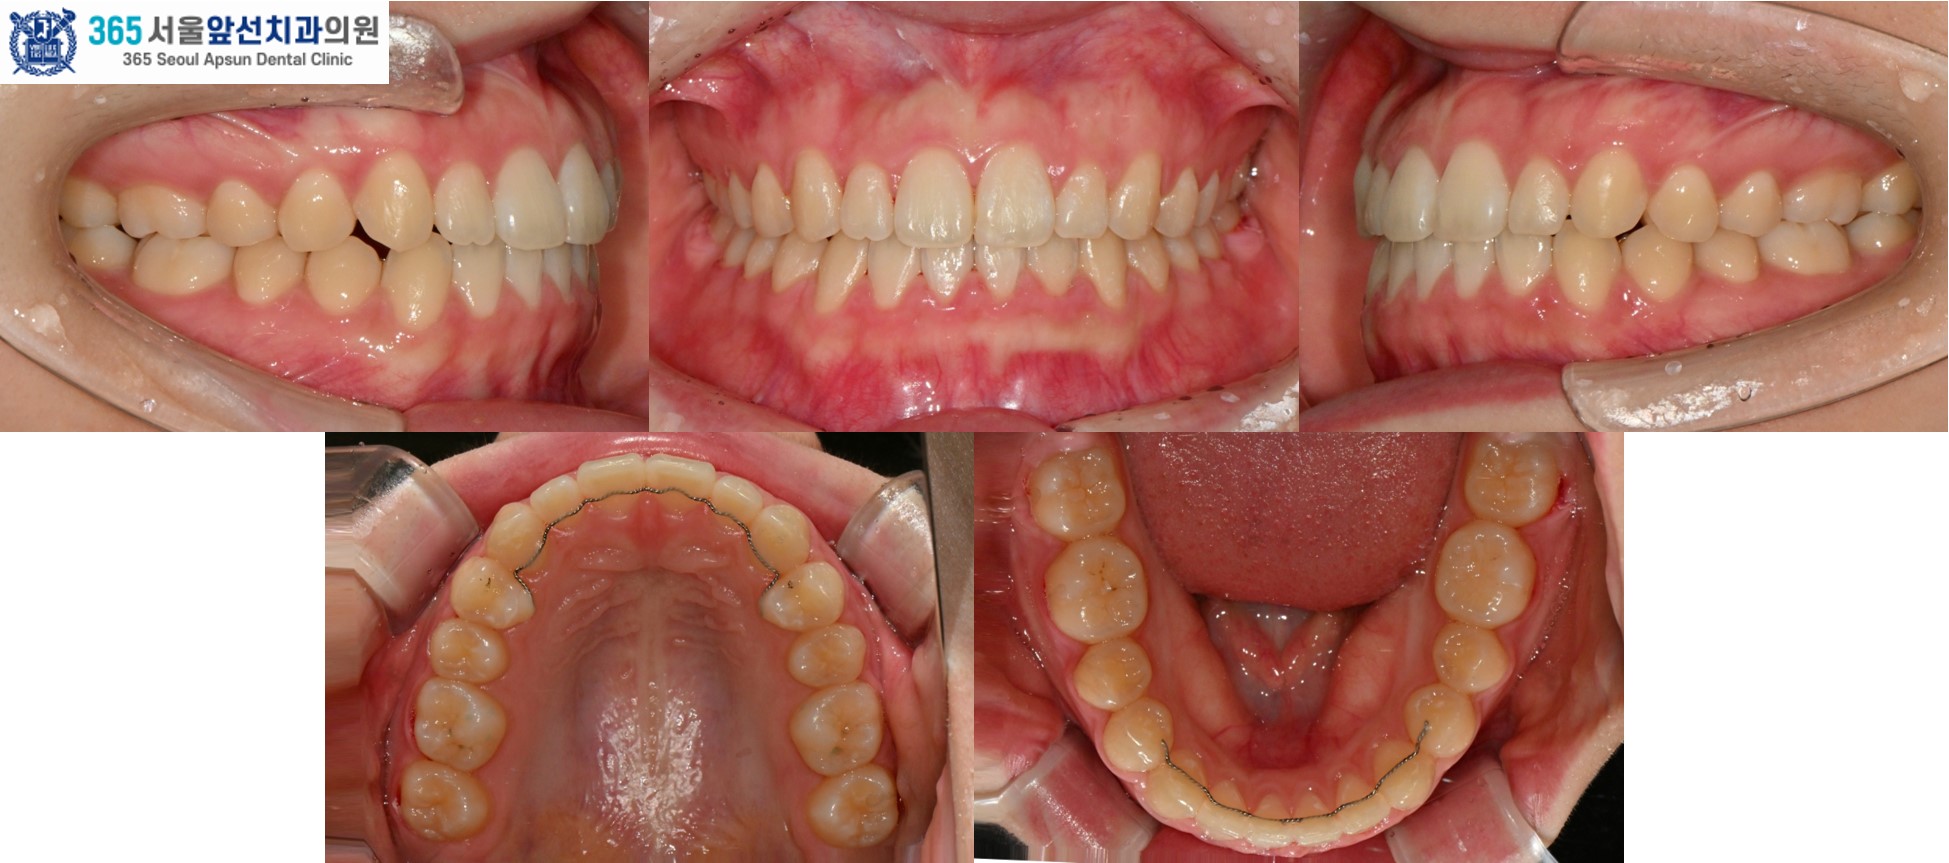

촬영일시 : 2024.10.23. 치료 전, 우측 측절치와 견치(송곳니)의 반대교합과 정중선 불일치가 관찰됩니다. 양측 상악 측절치가 5.6mm 폭경으로 왜소치 경향을 보이며 Bolton 의 전치부 비율이 86.73으로, 이상적인 윗니와 아랫니 앞니의 비율을 고려한 폭경에 비해 5.0mm가 부족합니다. 이 경우, 왜소치의 폭경을 키워 수복한다면 이상적인 교합을 형성할 수 있습니다. 해당 환자분께서는 왜소치의 수복 없이 치료하기를 원하셔서, 보상적으로 하악 치열의 폭경 감소와 Canine key compromise를 통해 최대한 심미적이고 기능적인 교합을 만들어드렸습니다.